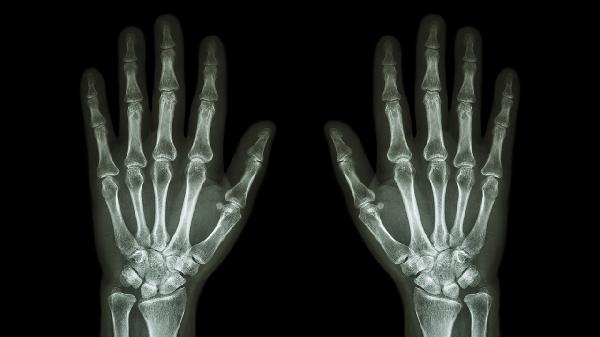

镉和化合物可以通过呼吸系统和消化系统进入身体。长期接触一定量的镉会对肾功能造成危害,主要表现为尿液中含有大量相对分子质量较低的蛋白质,由于肾小管损伤,导致钙、磷和维生素D代谢紊乱,导致骨增生变软松散,严重情况非常容易产生病理性骨折,严重影响患者的工作能力和生活质量。临床流行病的相关科学研究还提醒漫性镉中毒患者可能有中枢神经系统、人体免疫系统、泌尿系统和肿瘤。

3、导致高血压升高